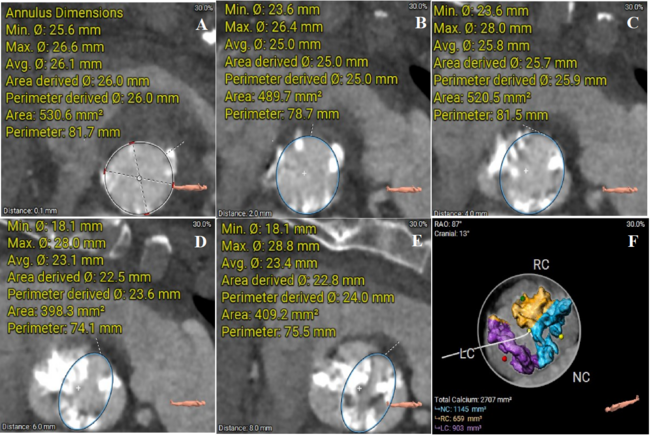

An 85-year-old woman was admitted to our hospital with severe symptomatic aortic stenosis. Preoperative computed tomography and transesophageal echocardiography (TEE) revealed a type I bicuspid aortic valve (aortic annulus diameter: 26 mm; Figure 1, Videos 1 and 2). After pre-dilation with an 18-mm balloon (Figure 2A, Video 3), a 26-mm self-expandable Taurus valve (PEIJIA Medical) was deployed (Figure 2B, Video 4). After valve expansion, post-dilation was performed using the 18-mm balloon (Figure 2C, Video 5). Aortography post-dilation indicated middle paravalvular leakage (Figure 2D, Videos 6 and 7), and the patient’s hemodynamics became unstable. TEE revealed cardiac tamponade and tissue swelling around the left sinus, with extensive calcification bulging out during post-dilation (Figure 3, Videos 8 and 9). Despite pericardial fluid drainage, autologous blood transfusion, and antagonizing anticoagulation (Figure 2E), the pericardial fluid increased in volume. After a second 26-mm valve was implanted within the first prosthesis (Figure 2F, Video 10), the patient’s hemodynamics stabilized. TEE revealed no increase in pericardial effusion and a decrease in the paravalvular leak (Video 11). Thus, valve-in-valve implantation may be an effective treatment to seal post-dilation-induced annular rupture during TAVR.